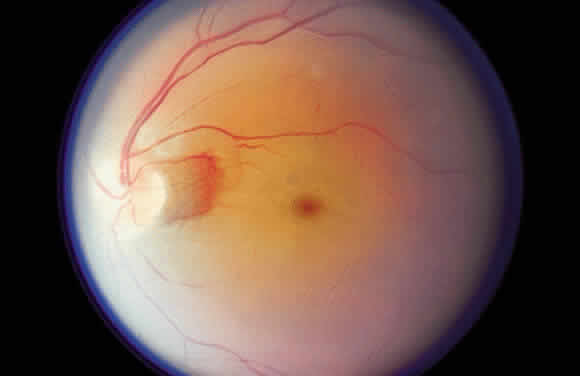

WHITE CHANGES IN THE FUNDUS Fibrous connective tissue appears white because of its collagen content. It

is not difficult to remember this relation, since the sclera is white. The

white appearance of a retinal choroidal coloboma, as an example

of collagen accounting for a white fundus appearance, already has

been cited. The temporal disc crescent seen in myopia is another example

of the ophthalmoscopist viewing the sclera directly (Fig. 15). In some cases of myopia, the pigment epithelium and choroid are stretched

to the point that they do not approximate the temporal margin of

the disc. The normally transparent retina does not contribute to the

color of this crescent. The black rim of the crescent is the contribution

of the retinal pigment epithelium.  Fig. 15. “Myopic crescent” in a patient with 9 diopters of myopia. Fig. 15. “Myopic crescent” in a patient with 9 diopters of myopia.